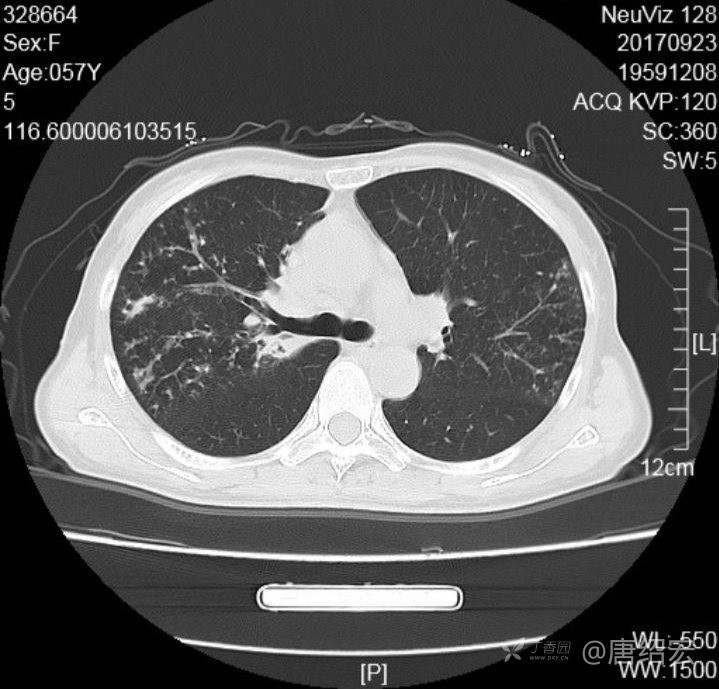

女,57岁,

主诉:发热、咳嗽、咯黄痰,胸闷3天入院。

铜绿假单胞菌性肺炎 (12)

铜绿假单胞菌感染 (20)